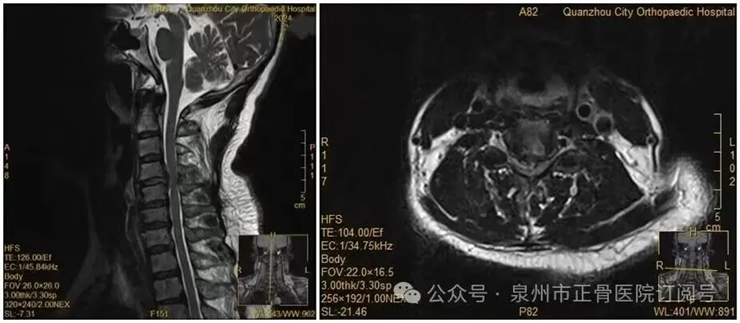

Bác sĩ cho biết, phim chụp cho thấy đĩa đệm cổ đã thoát vị rất lớn , hoàn toàn đủ chỉ định phẫu thuật, nên khuyến cáo bà cần can thiệp sớm. Tuy nhiên, do lo ngại rủi ro, bà Vương kiên quyết chọn điều trị bảo tồn , không phẫu thuật.

Kết quả kiểm tra cho thấy, trong ống sống đoạn C4- T1 tồn tại khối chiếm chỗ rất lớn , chèn ép tủy sống. Lúc này, từ ngực trở xuống A Đông hoàn toàn mất cảm giác , sức cơ hai tay cũng giảm rõ rệt. Bệnh viện lập tức kích hoạt luồng cấp cứu xanh , phẫu thuật ngay trong đêm để cứu khả năng vận động cho chàng trai trẻ.